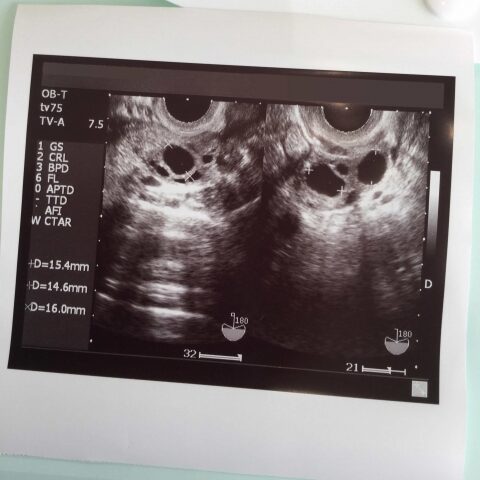

採血後に内診。いい感じで育ってるとのこと。卵胞の数は、左側に12〜17mmのものが4つと、右に?〜18mmのものが4つ。

こんなにたくさんの大きな卵胞は見たことが無く新鮮で、角度によっては蓮根の穴みたいに見えました。

卵胞の数は、左右5個ずつで、E2は2,200。卵胞的にはD13、ホルモン(E2)的にはD14と言われ、採卵日はD13に決まりました。この時のお腹の張りは、便秘4日目や食べ放題で満腹まで食べたほうが辛い程度。